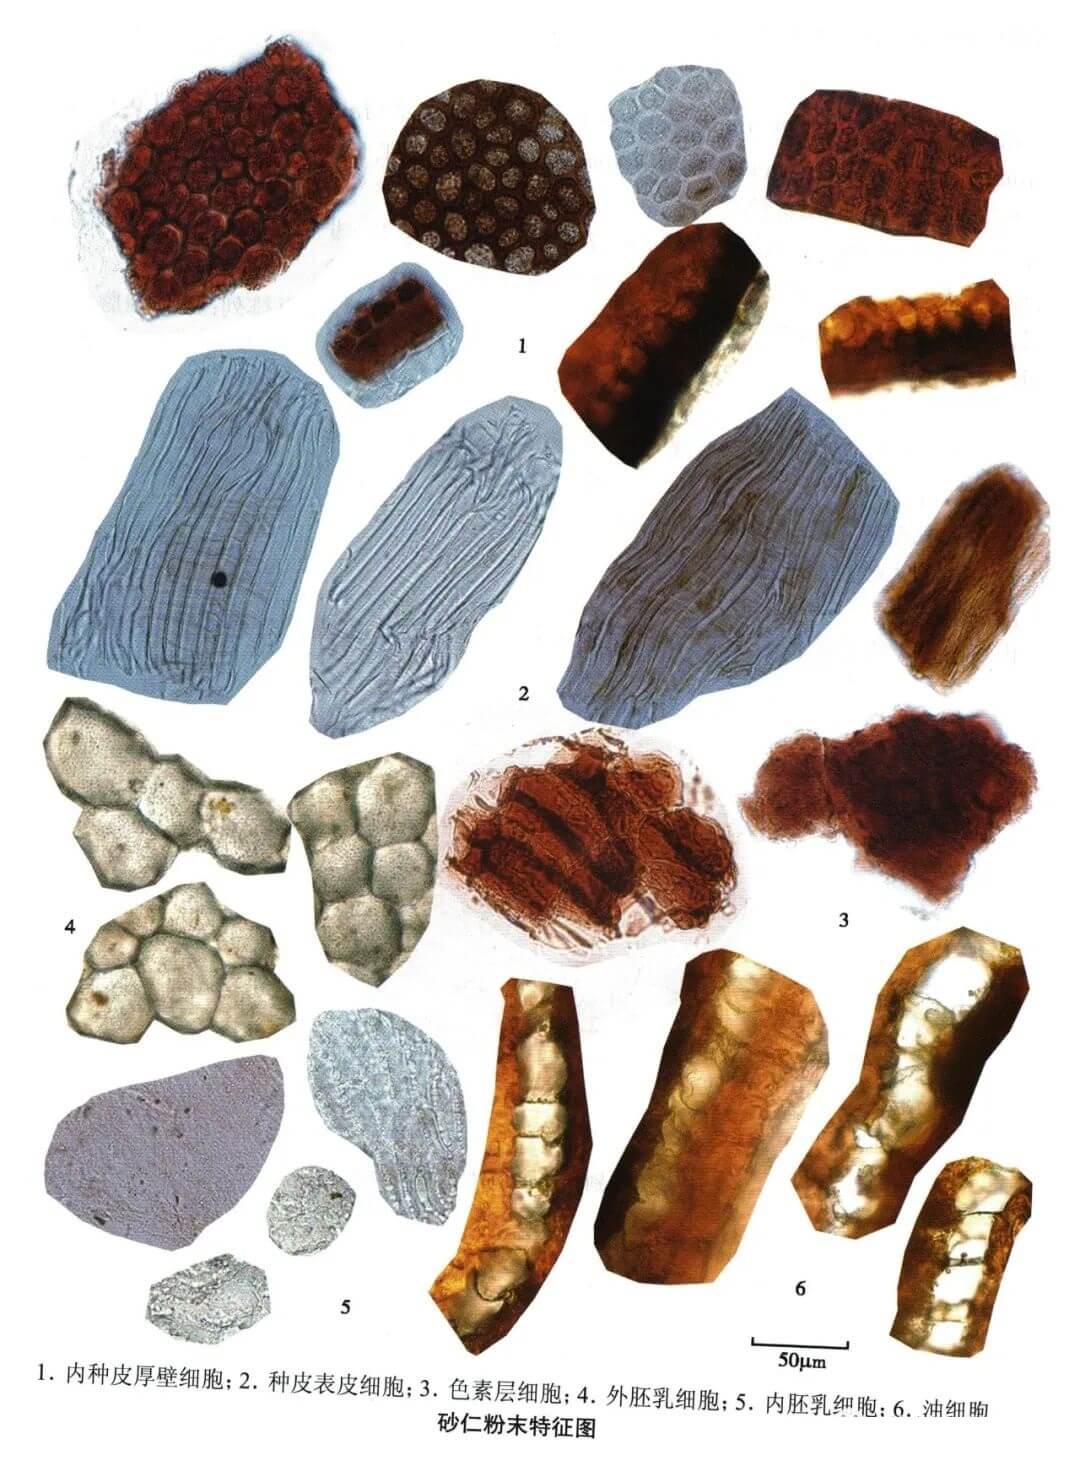

砂仁

| 砂仁 |

|---|

| 【参考标准】 《中国药典》2020年版 一部 |

| 【显微鉴别】 粉末灰棕色。内种皮厚壁细胞红棕色或黄棕色,表面观多角形,壁厚,非木化,胞腔内含硅质块;断面观为1列栅状细胞,内壁及侧壁极厚,胞腔偏外侧,内含硅质块。种皮表皮细胞淡黄色,表面观长条形,常与下皮细胞上下层垂直排列;下皮细胞含棕色或红棕色物。色素层细胞皱缩,界限不清楚,含红棕色或深棕色物。 |

| 【显微重点】 内种皮厚壁细胞表面管及断面观、种皮表皮细胞。 |

| 【图谱来源】 《中药成方制剂显微图典》 |